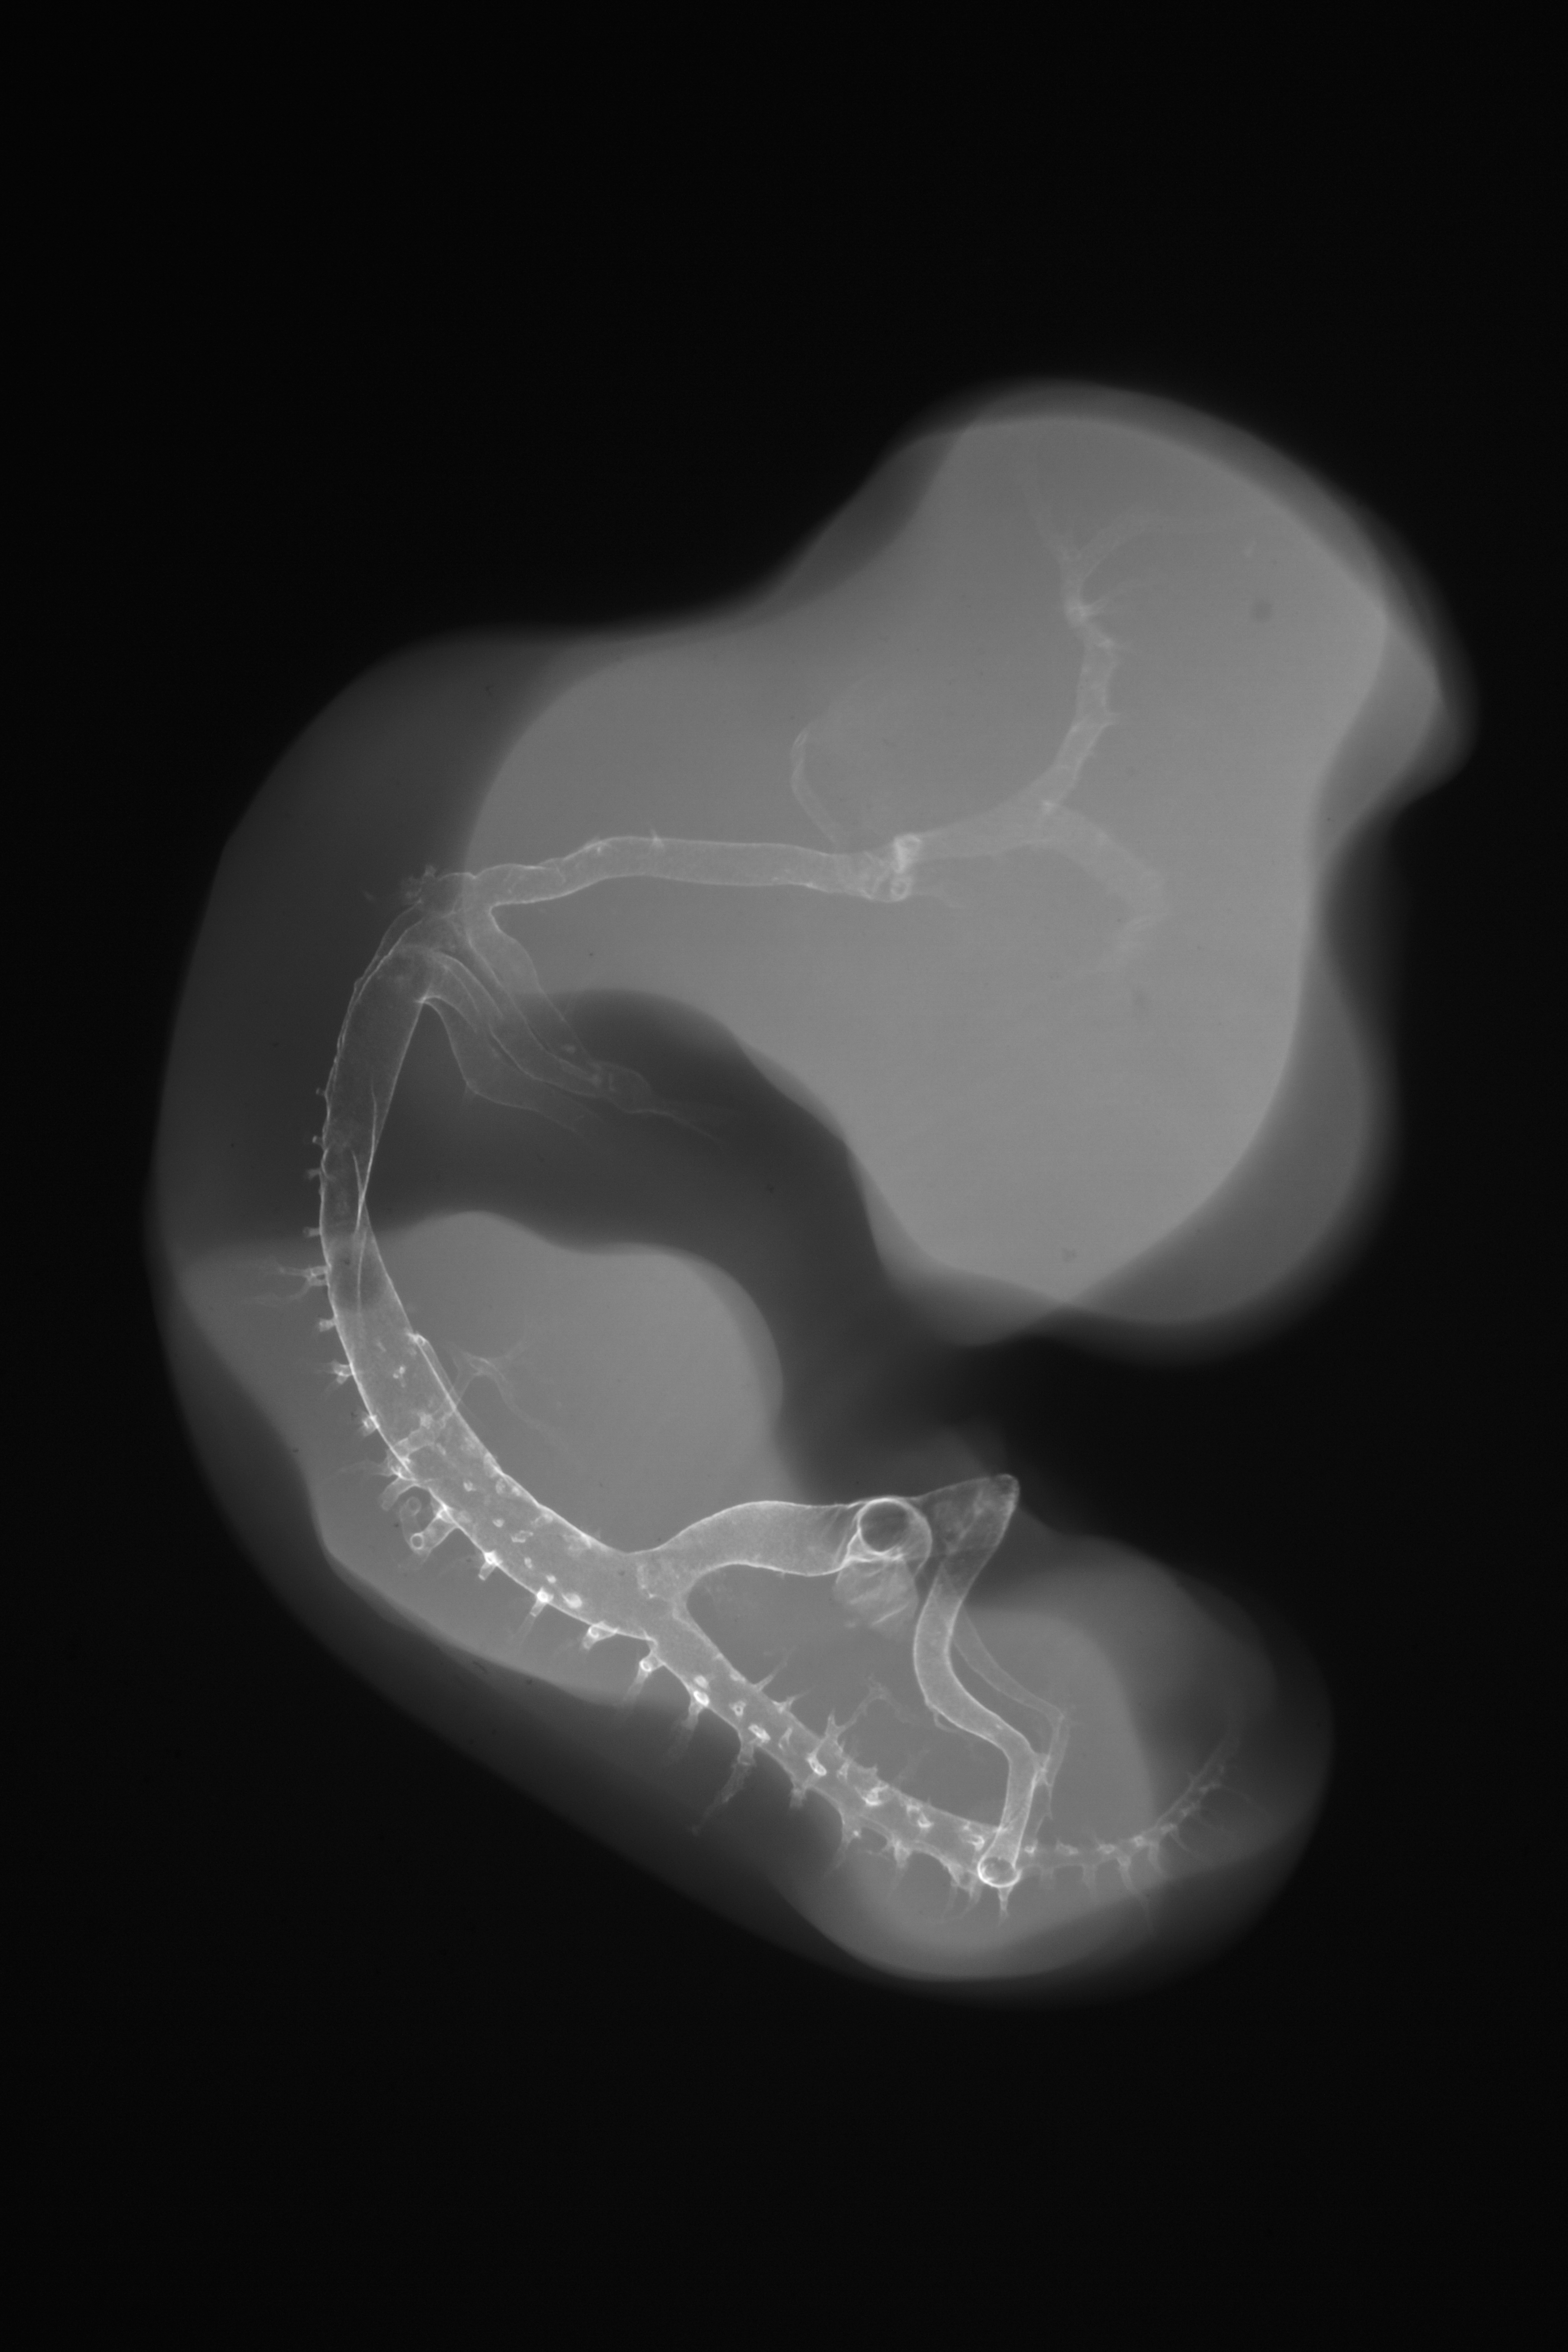

Chick Embryo Microangiography

Hamburger-Hamilton (HH) Stage 26 (approx. 5 days)

Stereo X-Ray Micrographs